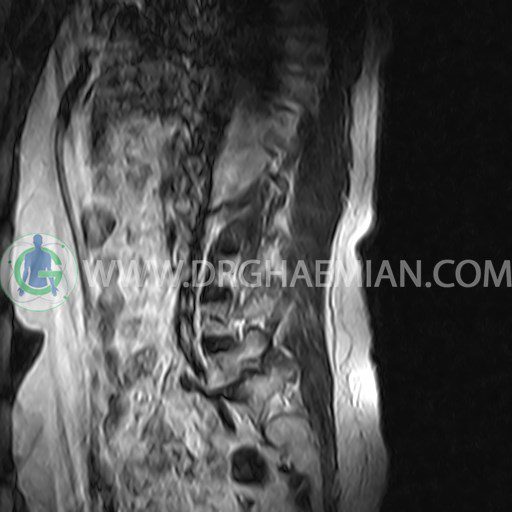

ام آر آی کمر از طریق انرژی آهنربا های قوی تصاویری از قسمت پایین ستون فقرات (گودی کمر) ایجاد می کند. در این کیس آنترولیستزیس کمر در مفصل L5/S1 به همراه اسپوندیلوز، تنگی فضای دیسک، دیهیدراته، بیرون زدگی و تنگی روزنه، همانژیوم کوچک در مهره L4، دیهیدراته، بیرون زدگی در دیسک L4/L5 دیده می شود.

LUMBOSACRAL SPINE MRI

Technique : Sagittal T1 , T2 , Axial T2 .

– Small hemangioma in L4

– L4/L5 disc dehydration, bulging and central annular fissure

– L5/S1 anterolisthesis grade 1 (with bilateral spondylolysis of L5), spondylosis, disc space narrowing, dehydration, bulging and foramina stenosis

are seen.